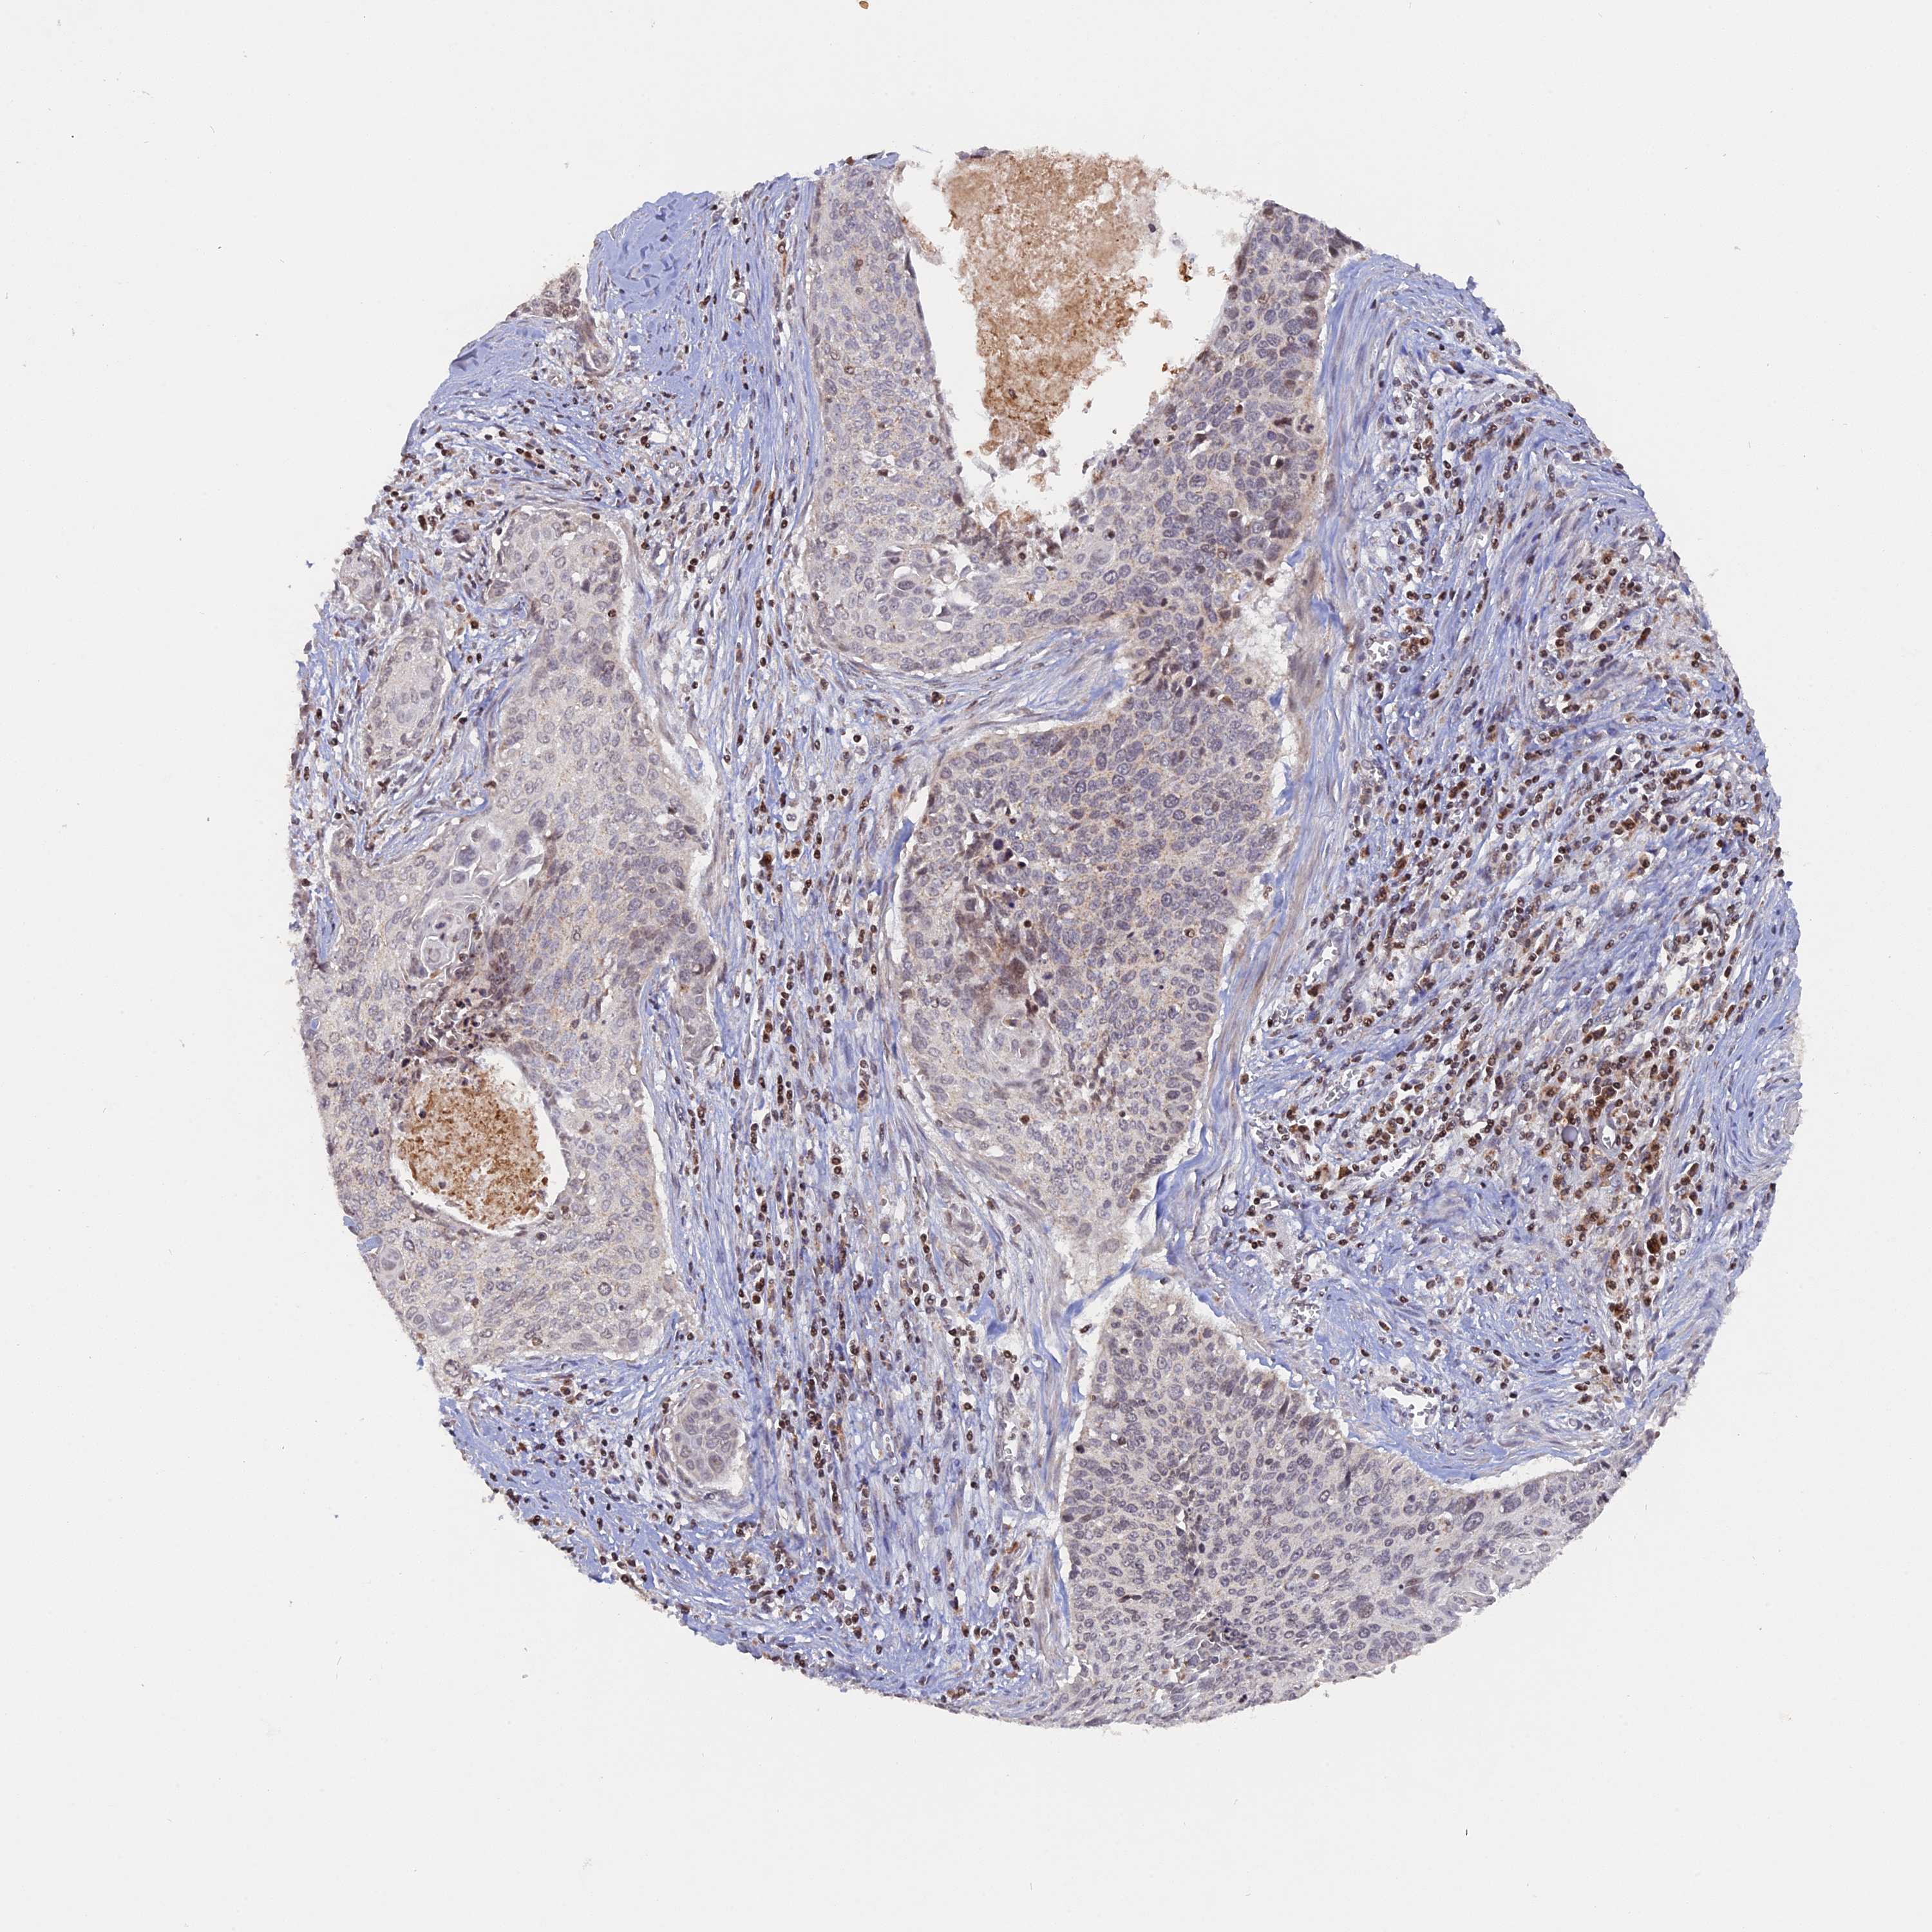

CERVICAL CANCER - Protein expressioni

A mouse-over function shows sample information and annotation data. Click on an image to view it in a full screen mode. Samples can be filtered based on level of antibody staining by selecting one or several of the following categories: high, medium, low and not detected. The assay and annotation is described here.

Note that samples used for immunohistochemistry by the Human Protein Atlas do not correspond to samples in the TCGA dataset.

Antibody stainingi

Antibody staining in the annotated cell types in the current human tissue is reported as not detected, low, medium, or high, based on conventional immunohistochemistry profiling in selected tissues. This score is based on the combination of the staining intensity and fraction of stained cells.

Each image is clickable and will lead to virtual microscopy that enables deeper exploration of all samples and also displays staining intensity scores, fraction scores and subcellular localization as well as patient and tissue information for each sample.

Antibody HPA041180

Staining

High

Medium

Low

Not detected

Intensity

Strong

Moderate

Weak

Negative

Quantity

>75%

75%-25%

<25%

None

Location

Nuclear

Cytoplasmic/membranous

Cytoplasmic/membranous,nuclear

Squamous cell carcinoma, NOS

Adenocarcinoma, NOS